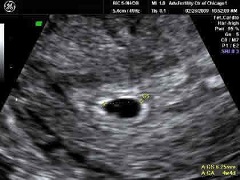

На УЗИ на 5 неделе беременности хорошо видно плодное яйцо, прикрепленное к стенке матки. Размеры его вместе с окружающими плодными оболочками и водами составляют около 1 см. При проведении УЗИ на 5 неделе беременности с применением аппаратов экспертного класса можно заметить первые сердечные сокращения, подтверждающие то, что зародыш живет и развивается.